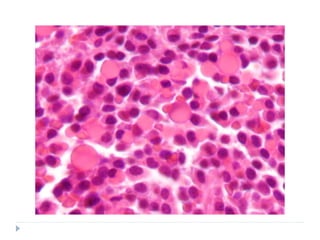

HISTOPATHOLOGY

 Monoclonal proliferation of B lymphocytes

 Lesion invades as broad sheets of tumour cells

 Tumour cells exhibit round nuclei with minimal

cytoplasm

 Each tumour nucleus has prominent nucleoli

 Numerous mitoses are seen

 At low power magnification: STARRY SKY PATTERN

is often appreciated

 STARRY SKY PATTERN

 Phenomenon that is caused by the presence of

macrophages within the tumour tissue

 Macrophages have abundant cytoplasm which

microscopically appears less stained in comparison with

the surrounding cells

 These macrophages also contain phagocytic debris

 THE MACROPHAGES THUS, STAND OUT AS STARS

SET AGAINST THE NIGHT SKY OF DEEPLY

HYPERCHROMATIC NEOPLASTIC LYMPHOID CELLS